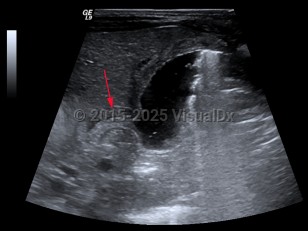

Imaging Studies image of Hypertrophic pyloric stenosis - imageId=7879501. Click to open in gallery.  caption: '<span>Hypertrophic pyloric stenosis  is seen on ultrasound image as  thickening of the pyloric muscle and  elongated pyloric canal length.</span>'

Hypertrophic pyloric stenosis is seen on ultrasound image as thickening of the pyloric muscle and elongated pyloric canal length.